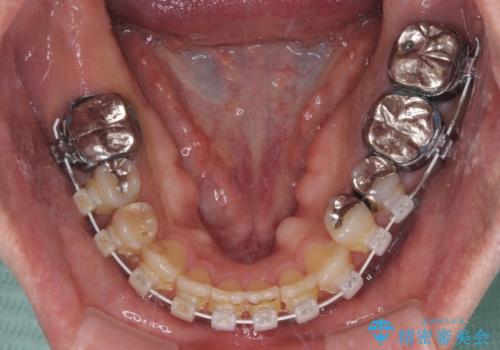

前歯の反対咬合が改善する過程では、奥歯が咬みにくくなるため、食事では辛い思いをされていたようです。

矯正治療後は安定した咬み合わせとなり、顎の違和感がなくなったとのことでした。